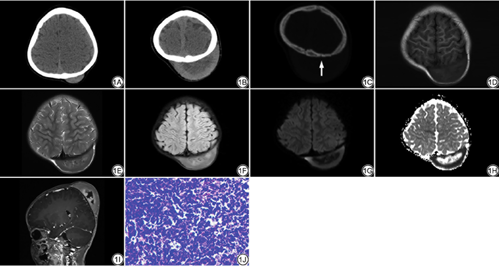

影像学检查示:半年前患儿头颅CT平扫:左侧顶部头皮下新月形软组织密度影,大小约3.3 cm×0.9 cm×3.6 cm,CT值约为52 HU (图1A)。本次入院头颅CT平扫(图1B~1C):左侧顶部头皮下类圆形软组织密度影,大小约5.5 cm×4.1 cm×7.1 cm,内部密度不均匀,CT值约为55 HU,邻近颅骨骨皮质毛糙、变薄。双侧多发颈部淋巴结增大。MRI检查:左顶部皮下一较大半圆形混杂信号,以等T1等T2信号为主,病灶中间呈片状混杂T1混杂T2信号(图1D~1E),FLAIR呈稍高信号(图1F),扩散加权成像(diffusion weighted imaging,DWI)呈中间不均匀低周围稍高信号(图1G),ADC图呈中间不均匀高周围稍低信号(图1H),增强扫描病灶中间呈低信号,周围呈较均匀强化(图1I),双侧枕部可见信号相似的软组织结节。影像诊断:多考虑恶性胚胎源性肿瘤,神经源性肿瘤不除外。

手术所见:行头皮下肿瘤切除术,术中见帽状腱膜下一巨大肿瘤呈灰红色,大小约5.0 cm×6.0 cm×4.0 cm,血供极其丰富,与周围组织粘连较重,侵蚀头皮帽状腱膜层,未及表皮,肿瘤相邻颅骨表面有侵蚀,肿瘤未见包膜。镜下见:肿瘤为淋巴样组织,瘤细胞中等偏小弥漫性分布,胞浆略嗜碱,核浆比增大,核膜清晰,核仁明显,核分裂像多见(图1J)。免疫组化染色:CD43 (+),CD79a (+),CD20 (+),PAX5 (+),TDT (-),CD10 (-),C-myc (+50%),CD3 (-),CD30 (-),ALK9 (-),Vim (-),EMA (-),CD99 (-),S100 (-),CD34 (-),Bcl-6 (-),Bcl-2 (-),Mum-1 (-),CD138 (-),CD56 (-),CD117 (-),Ki-67阳性细胞数98%。病理诊断:非霍奇金,B淋巴母细胞白血病/淋巴瘤。